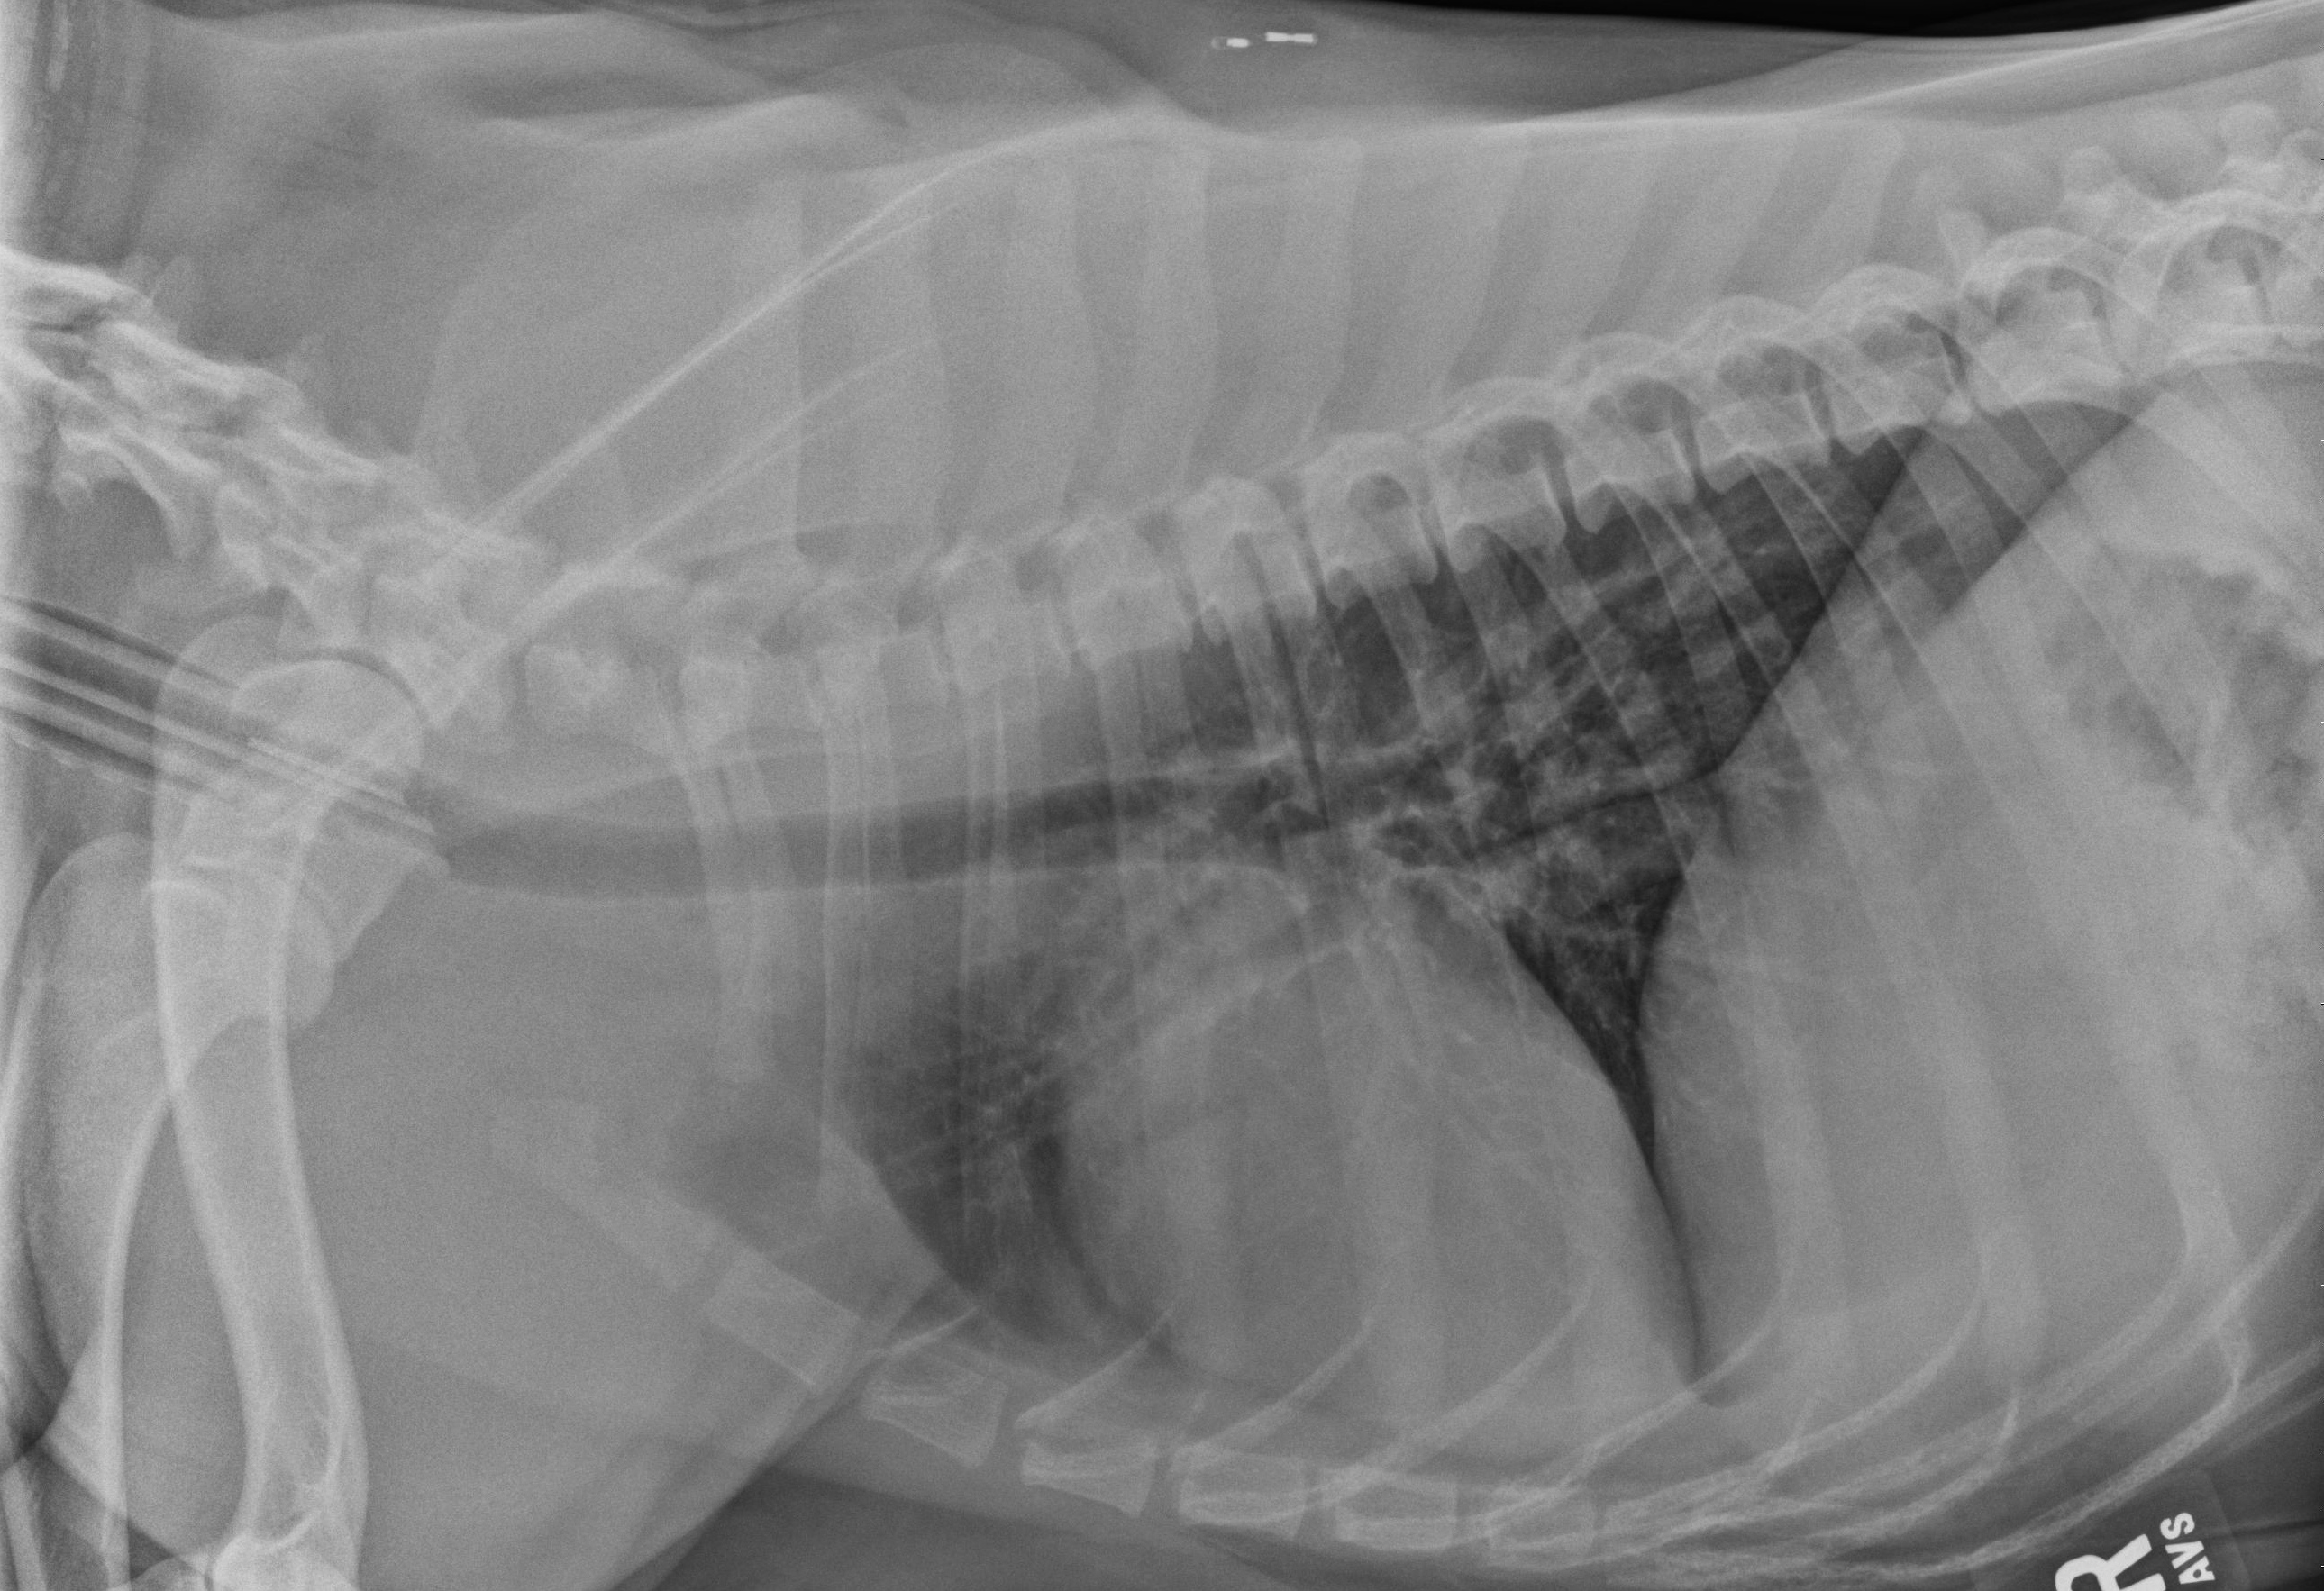

The next step for Luke was to perform some basic diagnostics including some radiographs (x-rays) of both his thorax (chest) and abdomen to rule out anything obvious or a communication from the outside into these body cavities. The x-rays were relatively unremarkable. With Luke under anesthesia just prior to surgery, a contrast study called a fistulogram was performed. A foley catheter was introduced into the non-healing wound and contrast fluid was injected. This fluid will show up white on x-rays. On this test, we were able to see some uptake of the contrast around an object in between the 11th and 12th rib. This test was very useful in showing us where we needed to focus our attention surgically.